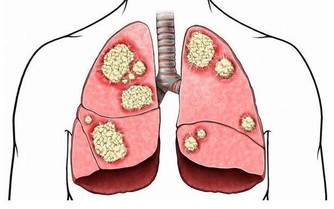

之前我寫過一篇《你覺得錢重要,還是健康重要?》的文章,看到有個朋友留言說,她曾因為晚睡,埋下病根,高考前突然爆發,花掉了家裡兩萬塊錢,住院半個月。進醫院的第一天做了很多檢查,期間還做了手術,直到現在都還需要進行定期檢查。

因為有了這樣的經歷,她告別了凌晨四點,現在基本上都不會超過晚上11點才睡覺了。